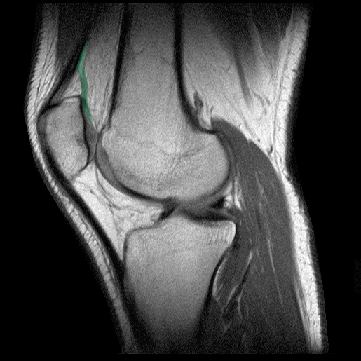

Definición: La bolsa subcuadricipital (bursa suprapatellaris) es la mayor de las 12 bolsas que existen en la rodilla. Se extiende entre el fémur y el cuadriceps y se comunica con la cavidad articular.

Origen: La bolsa subcuadricipital forma una "U" invertida, extendiéndose anterior al femur distal a lo largo de sus superficies medial y lateral.

Función: La bolsa subcuadricipital se comunica con la cavidad articular. Las efusiones de la articulación se vierten en la bolsa subcuadricipital de forma que la presencia de fluídos en dicha bolsa permite el diagnóstico de derrames.